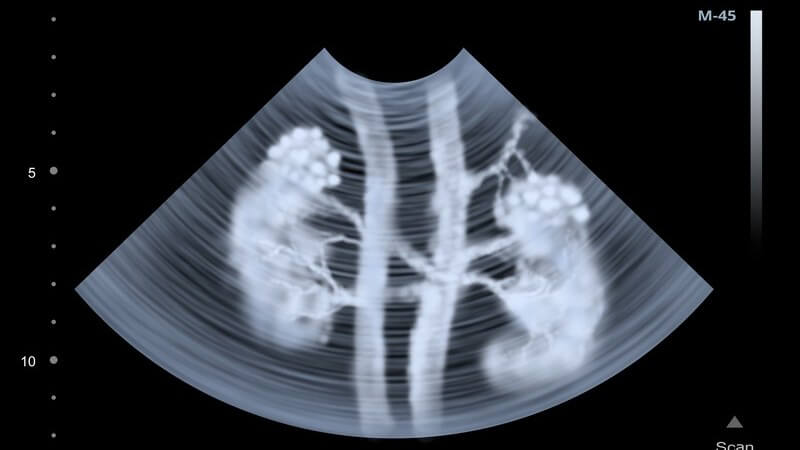

Die Nebennieren befinden sich am oberen Abschnitt der Nieren. Zu ihren Funktionen gehört die Produktion von verschiedenen Hormonen. Den äußeren Anteil der Nebennieren bezeichnet man als Nebennierenrinde. Dort entstehen Hormone wie

Um eine Überfunktion der Nebennieren festzustellen, untersucht man den Urin und das Blut des Patienten. Dabei achtet man besonders auf zu hohe Werte von Adrenalin und Noradrenalin.

Mögliche Diagnosemethoden